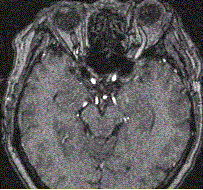

问题 女性,62岁。外伤后左侧突眼。MRI显示如下图。 需与该病鉴别诊断的疾病包括

选项 A.Tolosa-Hunt综合征 B.海绵窦神经鞘瘤 C.海绵窦脑膜瘤 D.海绵窦动脉瘤 E.海绵窦AVM F.海绵窦海绵状血管瘤

答案 ABCD